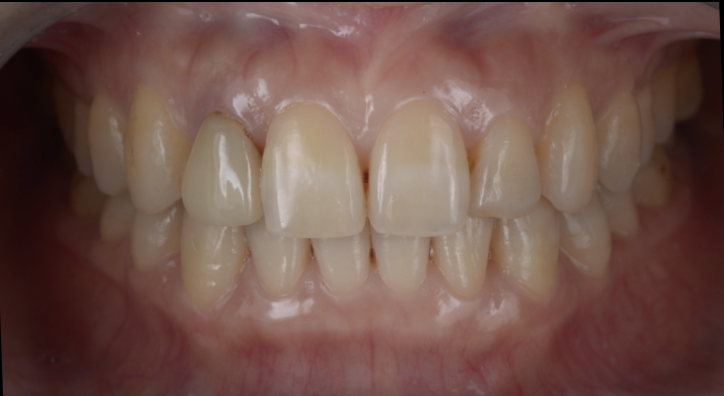

【40代 男性】

前歯の形が

変になってきた

- 担当医

- 生野 誠

- 主訴

- 前歯の形が変わってきた気がする

- 期間

- 3ヶ月

- 費用

- 48万

- 治療内容

- セラミックラミネートベニア

バイトアップ

- 治療に伴うリスク

- セラミックの脱離